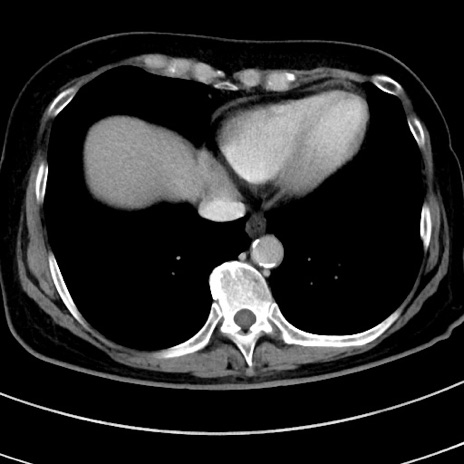

冠状断像

【症例】 60歳代女性

【主訴】むかつき、みぞおちの痛み

【現病歴】3日前よりむかつきがあり、食事がとれない。

【既往歴】糖尿病

【身体所見】発熱なし、心窩部圧痛軽度あるも、腹膜刺激症状なし。

【データ】WBC 7400、CRP 1.92